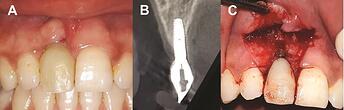

Retained cement results in peri-implantitis:

Retained cement results in peri-implantitis: ( A ) retained cement at the crown margin and excess cement in the peri-implant inflamed tissue, and ( B ) excess cement around the abutment. Reproduced from Ref. 23 with permission from John Wiley & Sons A/S.